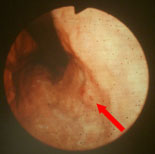

早期胃がん染色前 |

早期胃がん染色後 |